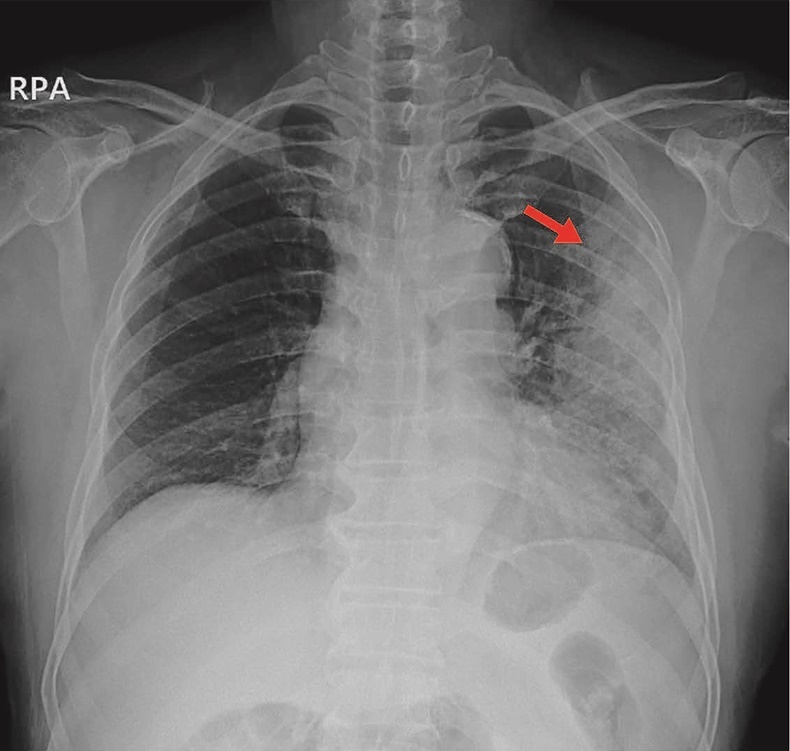

폐렴은 세균, 바이러스, 또는 곰팡이 감염으로 인해 폐에 염증이 생기는 질환입니다. 초기에는 감기와 비슷한 증상을 보이지만, 방치하면 호흡곤란, 패혈증 등 치명적인 합병증으로 이어질 수 있습니다. 특히 노인, 어린이, 그리고 면역력이 약한 사람들에게 더 위험하며, 조기 발견과 예방이 매우 중요합니다.